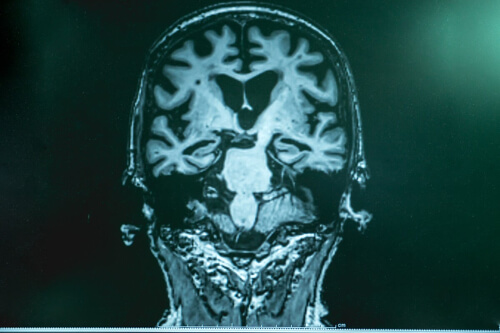

Fale gamma to wzorzec oscylacji neuronalnej, którego częstotliwość waha się między 20 a 100 Hz. Najbardziej typowa częstotliwość fal gamma manifestuje się w okolicach 40 Hz.

Fale te odzwierciedlają wysoką aktywność mózgu. Wyższą niż ta, którą wskazują fale beta, które pojawiają się, gdy znajdujemy się w stanie wysokiej koncentracji. Fale te wskazują, że mózg pracuje „na pełnych obrotach”, aktywując różne obszary mózgu.

Uważa się, że fale te aktywują się przez złożone funkcje wykonawcze lub wyższą aktywność umysłową. Chodzi o tak złożone czynności, jak orientacja, uwaga, świadomość lub procesy rozumowania… Wymagają one skoordynowanej aktywacji neuronów w różnych obszarach mózgu.

Otóż jak zbadano, aktywność gamma mózgu pacjentów z chorobą Alzheimera najwyraźniej ulega pogorszeniu. Może się to przyczyniać się do deficytów w złożonych funkcjach poznawczych, takich jak wspomniane powyżej.